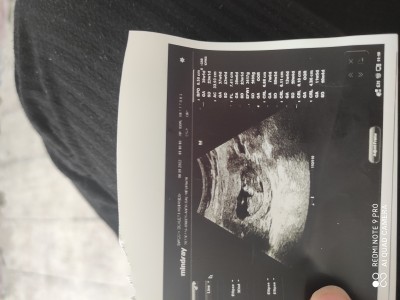

Bugün hastaneye gittim karabalik oldugundan birsey ogrenemedim bas popo mesafesi iyimi acaba degerlerden anlayan varsa bakabilirmisin

Gebelik haftası 11+5